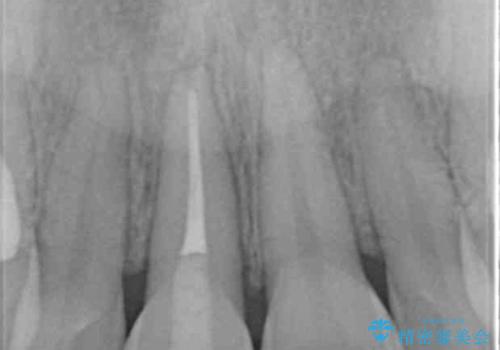

X線検査、歯髄(歯の神経)の検査を行ったところ、失活(歯の神経の死んだ状態)であると診断されました。

放置すると変色が進行するだけでなく、根尖病変も形成される恐れが強いことから、根管治療を行ったのちセラミッククラウンによる審美性の改善を計画します。